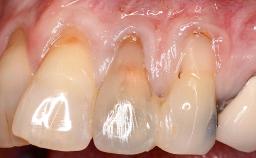

Soft-Tissue Volume Augmentation Using a Connective-Tissue Graft Harvested from the Maxillary Tuberosity

In 1983, a 51-year-old non-smoking patient was referred for the treatment of moderate chronic periodontitis. At the initial examination, 47% of sites exhibited probing depths of 4 to 6 mm. Periodontal therapy consisted of initial periodontal treatment including oral-hygiene instructions and supra- and subgingival debridement, followed by periodontal surgery to eliminate residual pockets.